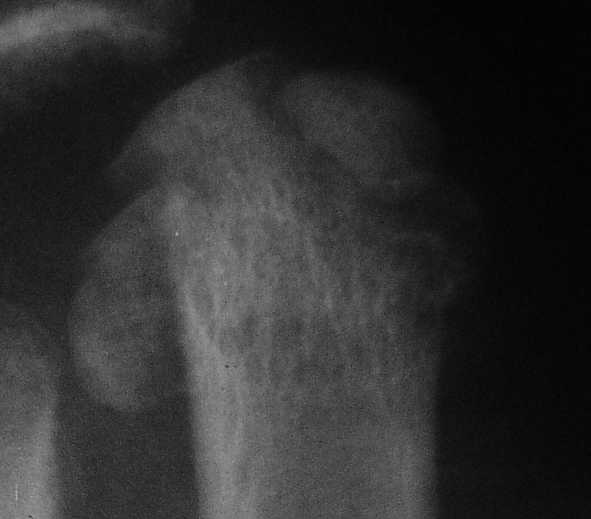

3 кстати, Вы перелом пкрвой плюсневой видите? В каком месте и на каком снимке?

Вот головка более прицельно.

Вот теперь вижу :)

предлагаю. Все то же самое плюс по обстоятельствам, в зависимости от внутриоперационных находок- либо ничего не делаем, либо фиксируем фрагмент спицей ( можно даже адсорбируемой - получим пласмассоостеосинтез:)) или микрошурупом, либо - если вправление пойдет совсем плохо - все же как минимум восьмая неделя - эксцизионная пластика сустава .